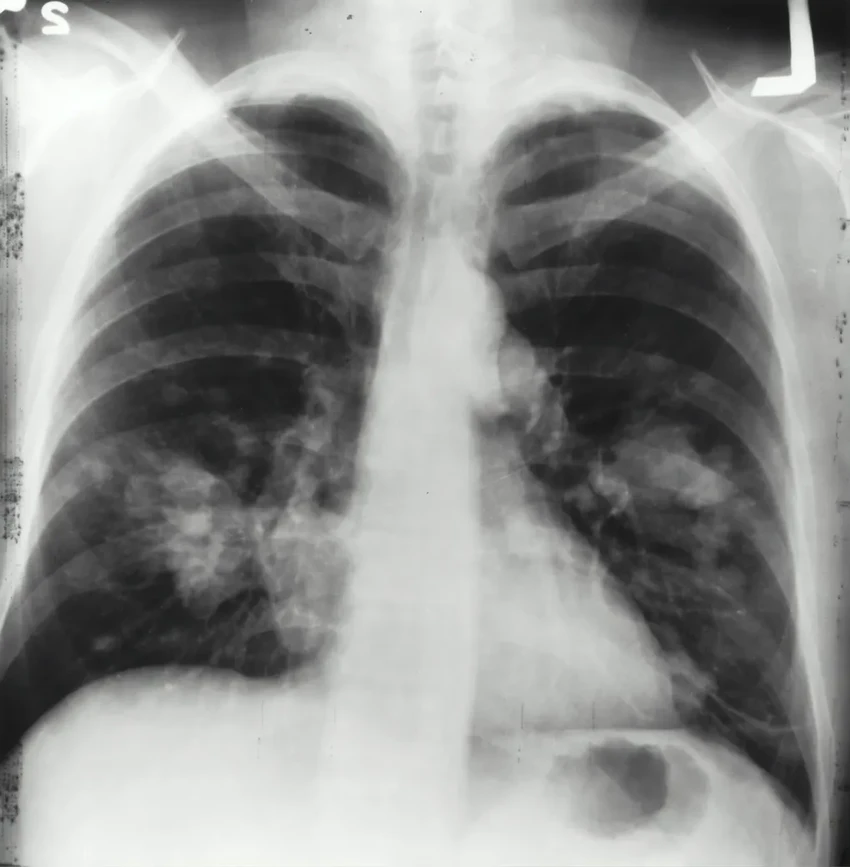

Цифры, увы, безрадостны. По прогнозам Американского онкологического общества, только в этом году в США рак легких диагностируют у более чем 230 тысяч человек. Около половины из них болезнь унесет. Особенно сложно бороться с опухолями, которые развили устойчивость к стандартной терапии.